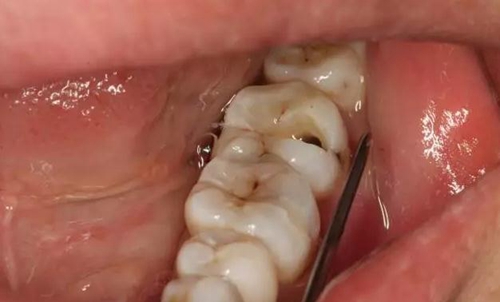

圖1.患者自述右側(cè)下后牙牙齦紅腫,咀嚼不適。術(shù)前口內(nèi)像:37頰側(cè)牙齦紅腫

10.jpg